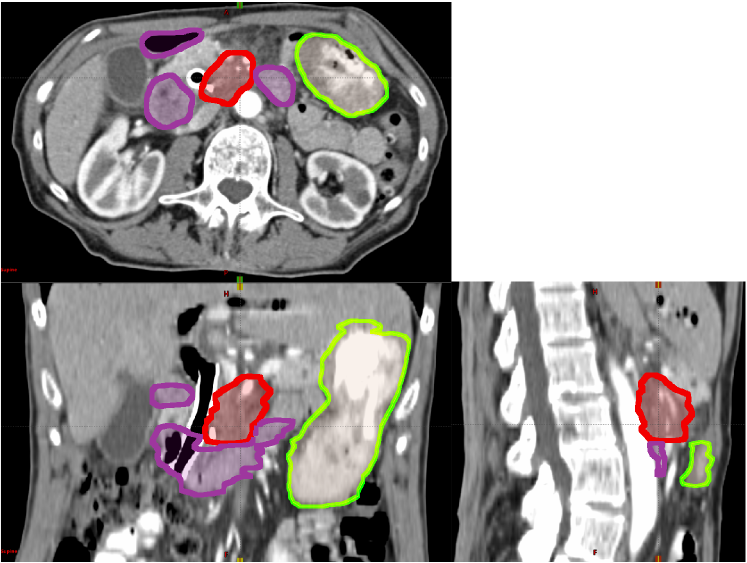

However, dose escalation is limited by toxicities to the surrounding organs at risk (OARs). OARs in pancreatic SBRT include stomach and duodenum [19], because they are highly sensitive to radiation and adjacent to the pancreas. The location of tumor, duodenum and stomach in one patient are shown in Figure 1. Due to breathing, digestion, and heartbeat, the boundary between the tumor and nearby OARs is blurred. This internal target movement may lead to underdosage in parts of the tumor and overdosage to the OARs. As dose to the tumor escalates, these dose differences will grow larger, potentially increasing toxicity and decreasing local control.

Refer to caption

Figure 1: The location of pancreatic tumor (GTV, red), duodenum (purple) and stomach (green) for a patient on a 3D CT scan.

Between November 2015 and July 2017, we treated 25 newly diagnosed pancreatic adenocarcinoma cases with Volumetric Modulated Arc Therapy (VMAT) to a dose of 33 Gy in five fractions using 6—10 MV photons. More details regarding these treatments can be found in a prior study [21]. Patients underwent two sets of CT scans prior to treatment: a free-breathing three-dimensional computed tomography (3D CT) scan for target definition and dose calculation and a four-dimensional CT (4DCT) scan to assess respiratory motion. Two motion-mitigation techniques were used during simulation and treatment. In 7 patients, abdominal compression was used during simulation and treatment to reduce the amplitude of motion. In the remaining 18 patients, respiratory gating was used. Gross tumor volumes (GTV) were drawn by the radiation oncologist on the planning CT (as shown in red in Figure 1), and expanded to create a Planning Target Volume (PTV). The GTV-to-PTV expansion margins were typically 3-5 mm, and were determined by the oncologist based on local anatomy. PTV volumes were trimmed to avoid overlap with OARs. An Internal Target Volume (ITV) was not used; however, motion was taken into account in the design of the PTV. For this, the PTV contour was overlaid on the 4DCT, and compared against the observed range-of-motion of the tumor boundaries. For patients managed with gating, the range-of-motion included only the 30%percent\% to 70%percent\% phases of the 4DCT (end-exhale phases); whereas for patients managed with compression, this motion included all phases. If needed, the PTV was expanded further to encompass this range of motion. The EclipseTM Treatment Planning System (Varian Medical Systems, Palo Alto, CA) was used for planning and dose calculation. Data from these clinical cases were analyzed under an institutional review board (IRB) approved retrospective research protocol.